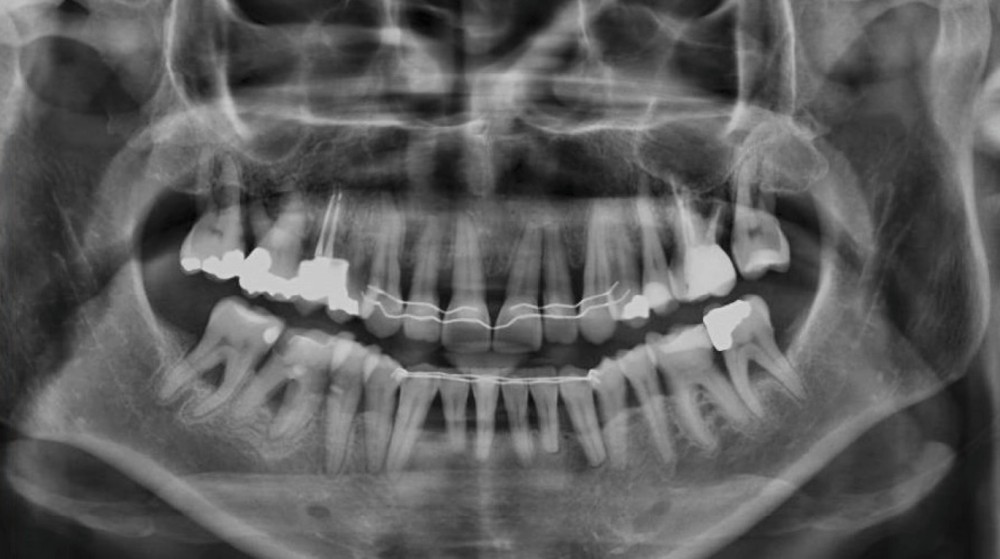

L’examen radiographique (fig. 3-5) nous indique une Classe I squelettique de Ballard (ANB 0°) sur un schéma facial à tendance hyperdivergent (FMA 28°). L’analyse céphalométrique confirme la vestibulo-version incisive (I/SN 111° ; IMPA 94°). La lyse osseuse est généralisée.